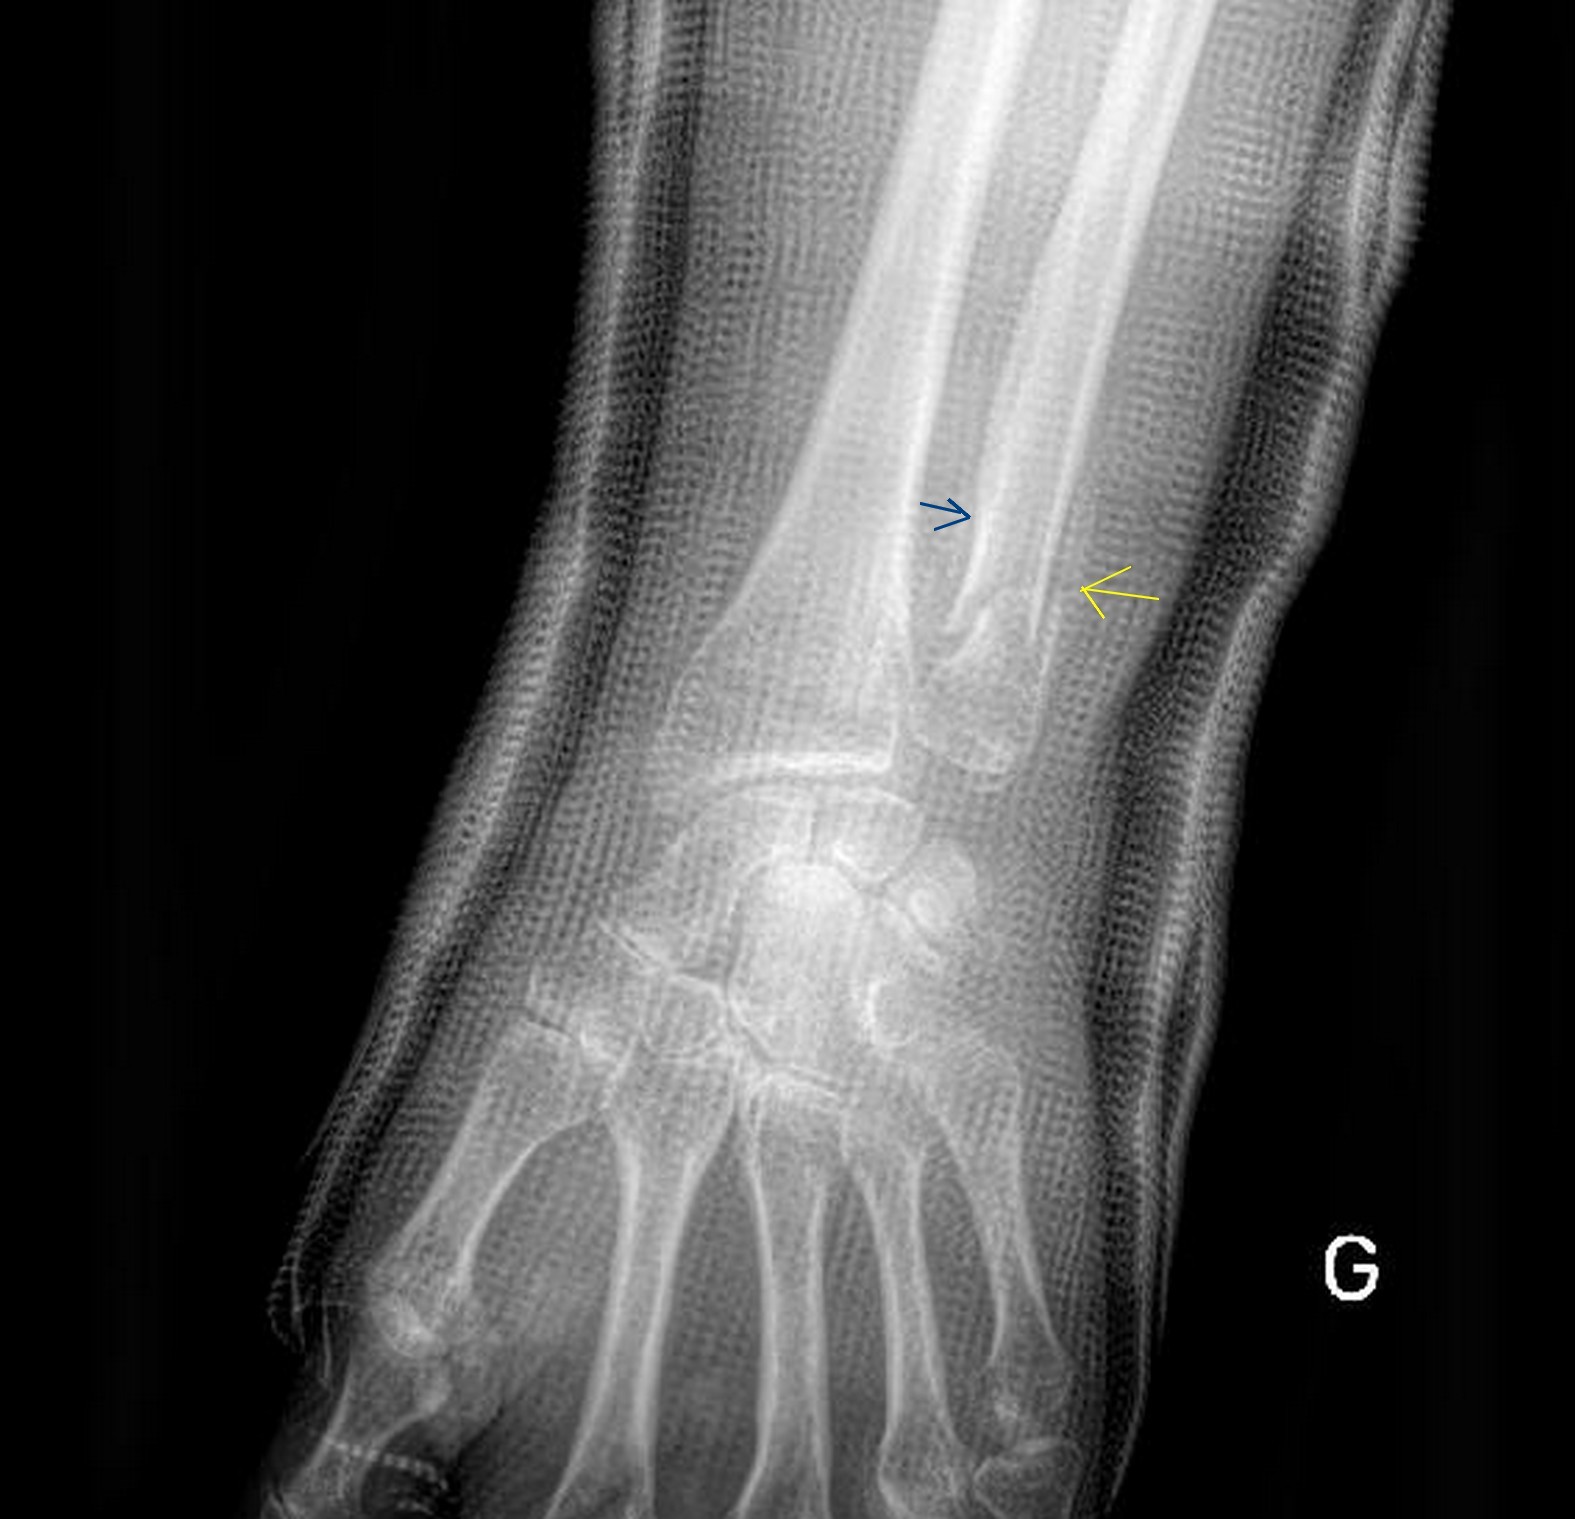

Dans l’article précédent je vous ai laissé dans l’attente de mon RDV avec la chirurgienne le vendredi 13 août. Et donc voici les nouvelles. Cette dame très sympathique et à l’écoute m’a montré sur ma radio un morceau blanc sur le coté de l’os, flèche bleue, ce qui veut dire que la consolidation a bien commencé.

Donc on ne touche pas ! Et enfin plus de plâtre youpi. Bien sur une attelle tout de même et pour 15 jours au moins.